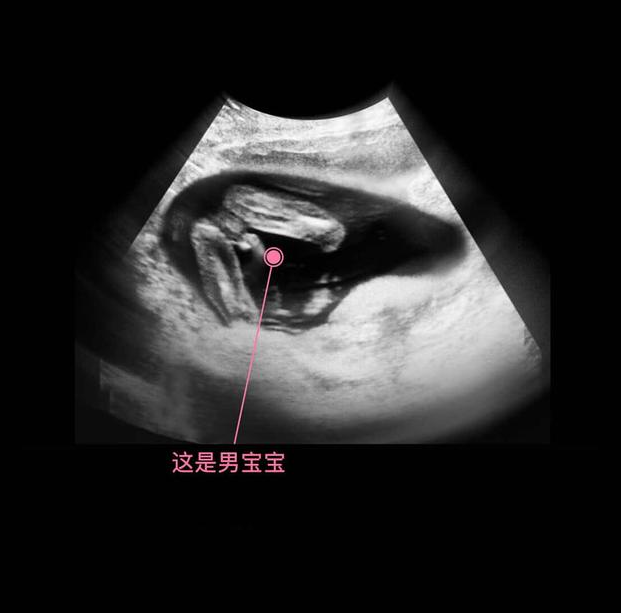

其实从孕9周开始,胎儿的性别就开始分化,孕17周,B超扫描清晰可见胎儿的性别,不过也有的宝宝因为胎位的原因,或者脐带遮挡,让医生产生了误判,男女会出现翻盘的可能呢。